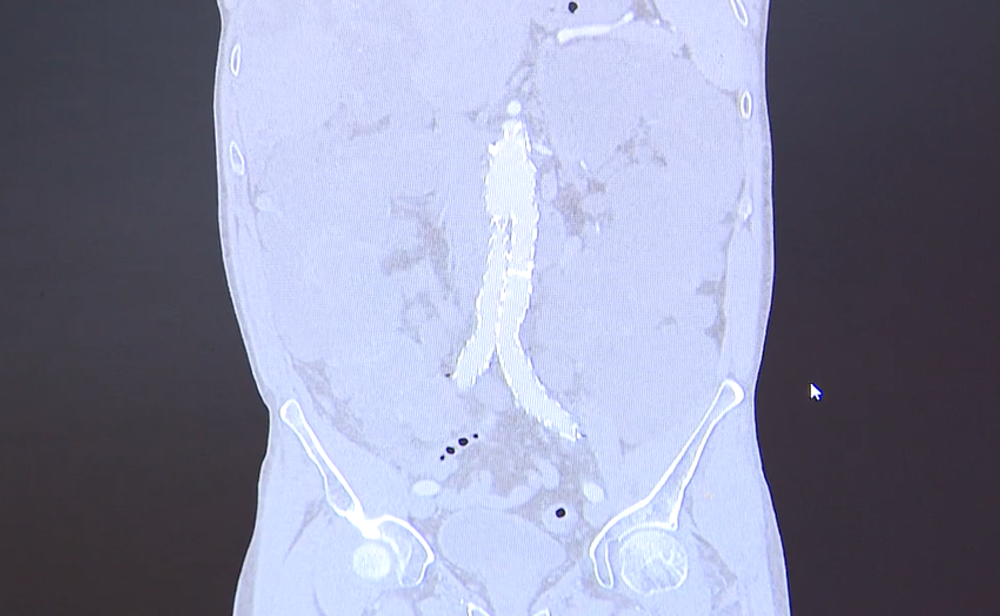

Unikátny zákrok: Na sále vlastnoručne ušili pacientovi protézu

Screenshot 2024-08-10 094507

Zdroj: TV JOJ